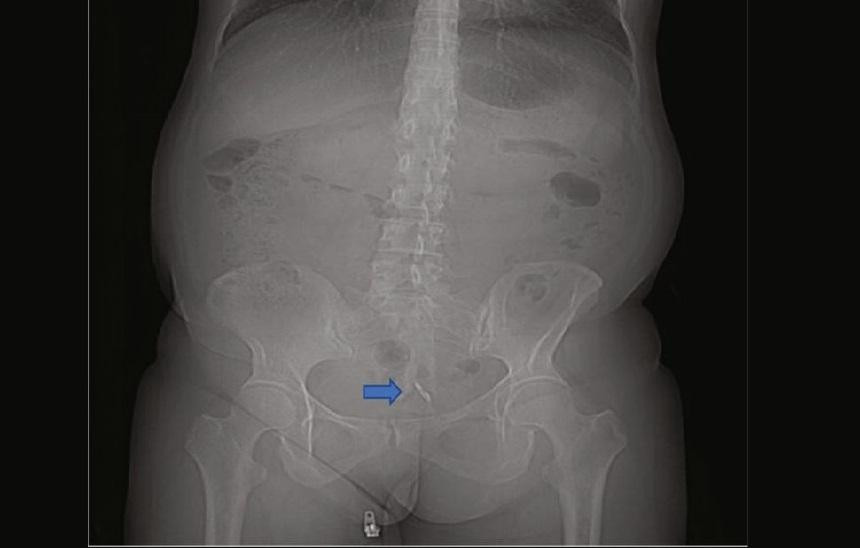

Vòng tránh thai lạc vào bàng quang

| Vòng tránh thai được phát hiện trong bàng quang người phụ nữ |

Vòng tránh thai được coi là hình thức ngừa thai hiệu quả có thể kéo dài đến 12 năm. Nhưng trong một số trường hợp hiếm hoi, thiết bị này có thể làm thủng tử cung với tỉ lệ 1/1000 phụ nữ đặt vòng tránh thai. Thế nhưng, việc vòng tránh thai làm thủng bàng quang rất hiếm. Đó là trường hợp của một phụ nữ 47 tuổi, bị đi tiểu ra máu. Hóa ra, chiếc vòng tránh thai 10 năm trước cô sử dụng đã lọt khỏi tử cung và vào bàng quang. Các bác sỹ đã phát hiện một viên sỏi bàng quang được hình thành trên một phần của chiếc vòng tránh thai này và họ đã phải tán sỏi bàng quang và lấy vòng tránh thai ra.